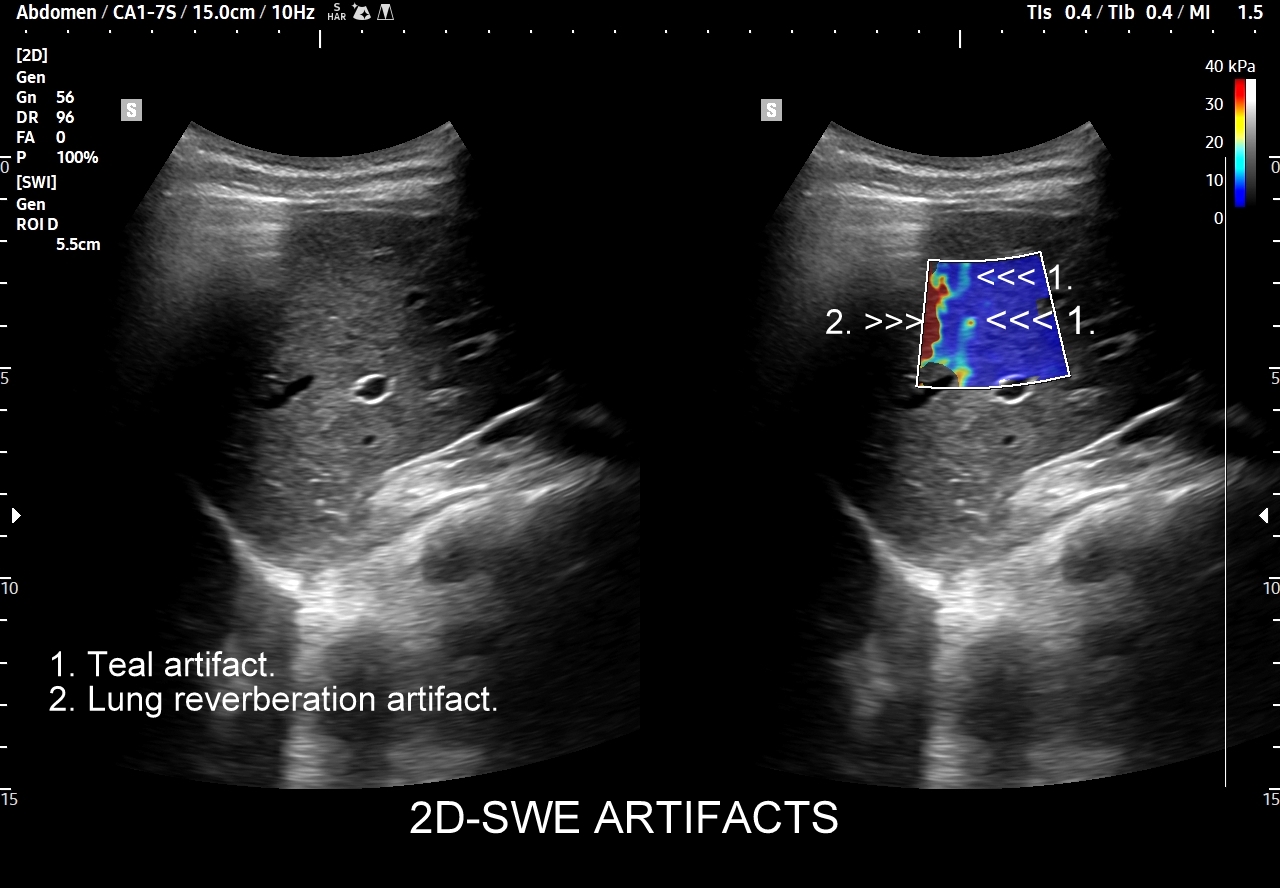

- Elastografia wątroby.

Multiparametryczne badanie USG (MPUS) jest rozwinięciem klasycznego USG jamy brzusznej zwykle w formie jednoczasowego zastosowania różnorodnych technologicznie trybów obrazowania USG, zarówno tzw. „nowych”, jak i „starych”. Wśród nowych najważniejszym jest obrazowanie mikrounaczynienia (MVI / MVF), a w dalszej kolejności tryby elastograficzne oraz metody ilościowej oceny stłuszczenia wątroby. Wymienione „nowe” modalności w połączeniu ze „starymi”, przede wszystkim z Dopplerem spektralnym i color-Dopplerem, stanowią rdzeń nowoczesnej ultrasonografii MPUS, gdyż umożliwiają pozyskanie znacznie większej ilości informacji z badania USG w porównywalnym przedziale czasowym, a przez to uzyskanie jego większej wartości diagnostycznej. Przykładowo badanie MPUS umożliwia różnicowanie pseudoguzów od guzów prawdziwych, ocenę żywotności tkanek, biologii nowotworów, funkcjonalną ocenę nerek i wątroby, poprawia obrazowanie dużych naczyń krwionośnych oraz charakterystykę podejrzanych torbieli.